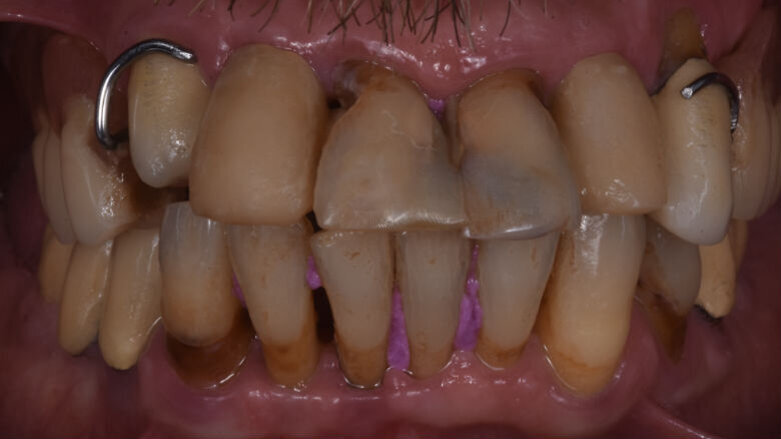

Il paziente in questione è un uomo di 55 anni riferito alla nostra attenzione da un collega che era in cura presso il nostro studio. La situazione (Fig. 1) si presentava molto critica, le tasche parodontali eccedevano i 6 mm e gli indici di placca e sanguinamento lasciavano poche speranze ai denti rimasti sull’arcata superiore. L’utilizzo di una protesi rimovibile appoggiata su elementi parodontalmente compromessi aveva causato lo sventagliamento di tutti i denti residui, questo oltre a causare una grave instabilità produceva anche un effetto molto poco estetico.

Il paziente in questione richiedeva, se possibile, una sostituzione dei denti tramite una protesi fissa per avere un miglior risultato sia estetico che funzionale.